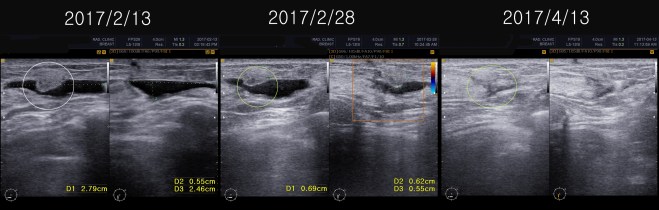

• 2016년 9월 8일  2.3cm(2016/5/26) —-> 1.13cm(2016/9/8)

• 2016년 10월 13일 약 10mm  x 2mm의 종양의 괴사된 흔적 남아 보임

이후 방사선이 끝나고 내원하여 9월 달 보니 종양의 거의 괴사되어서 1.13×0.58cm의 크기가 남아 있었고 한달 뒤인 2016년 10월 13일에는 1.03×0.2cm 정도의 괴사된 흔적만 보였다.

이 환자는 1년간 내 치료를 잘 따라 주었고 마음이 안정이 되어서 현재 사회생활도 하고 있다. 5월중에 초음파를 다시 비교하였다. 2017년 1월달에 추적검사를 하였고 다시금 5개월 뒤에 추적검사를 하였다.

• 2016 년 9월 8일    2.3cm(2016/5/26) —->  1.13cm(2016/9/8)

• 2016 년  10월 13일   약 10 mm  x 2 mm 의  종양의 괴사된 흔적 남아 보임.

이후 방사선이  끝나고  내원하여  9월 달  보니 종양의 거의 괴사되어서 1.13x  0.58 cm 의 크기가 남아 있었고  한달 뒤인  2016년 10월 13일에는  1.03 x 0.2cm 정도의 괴사된 흔적만 보였다.